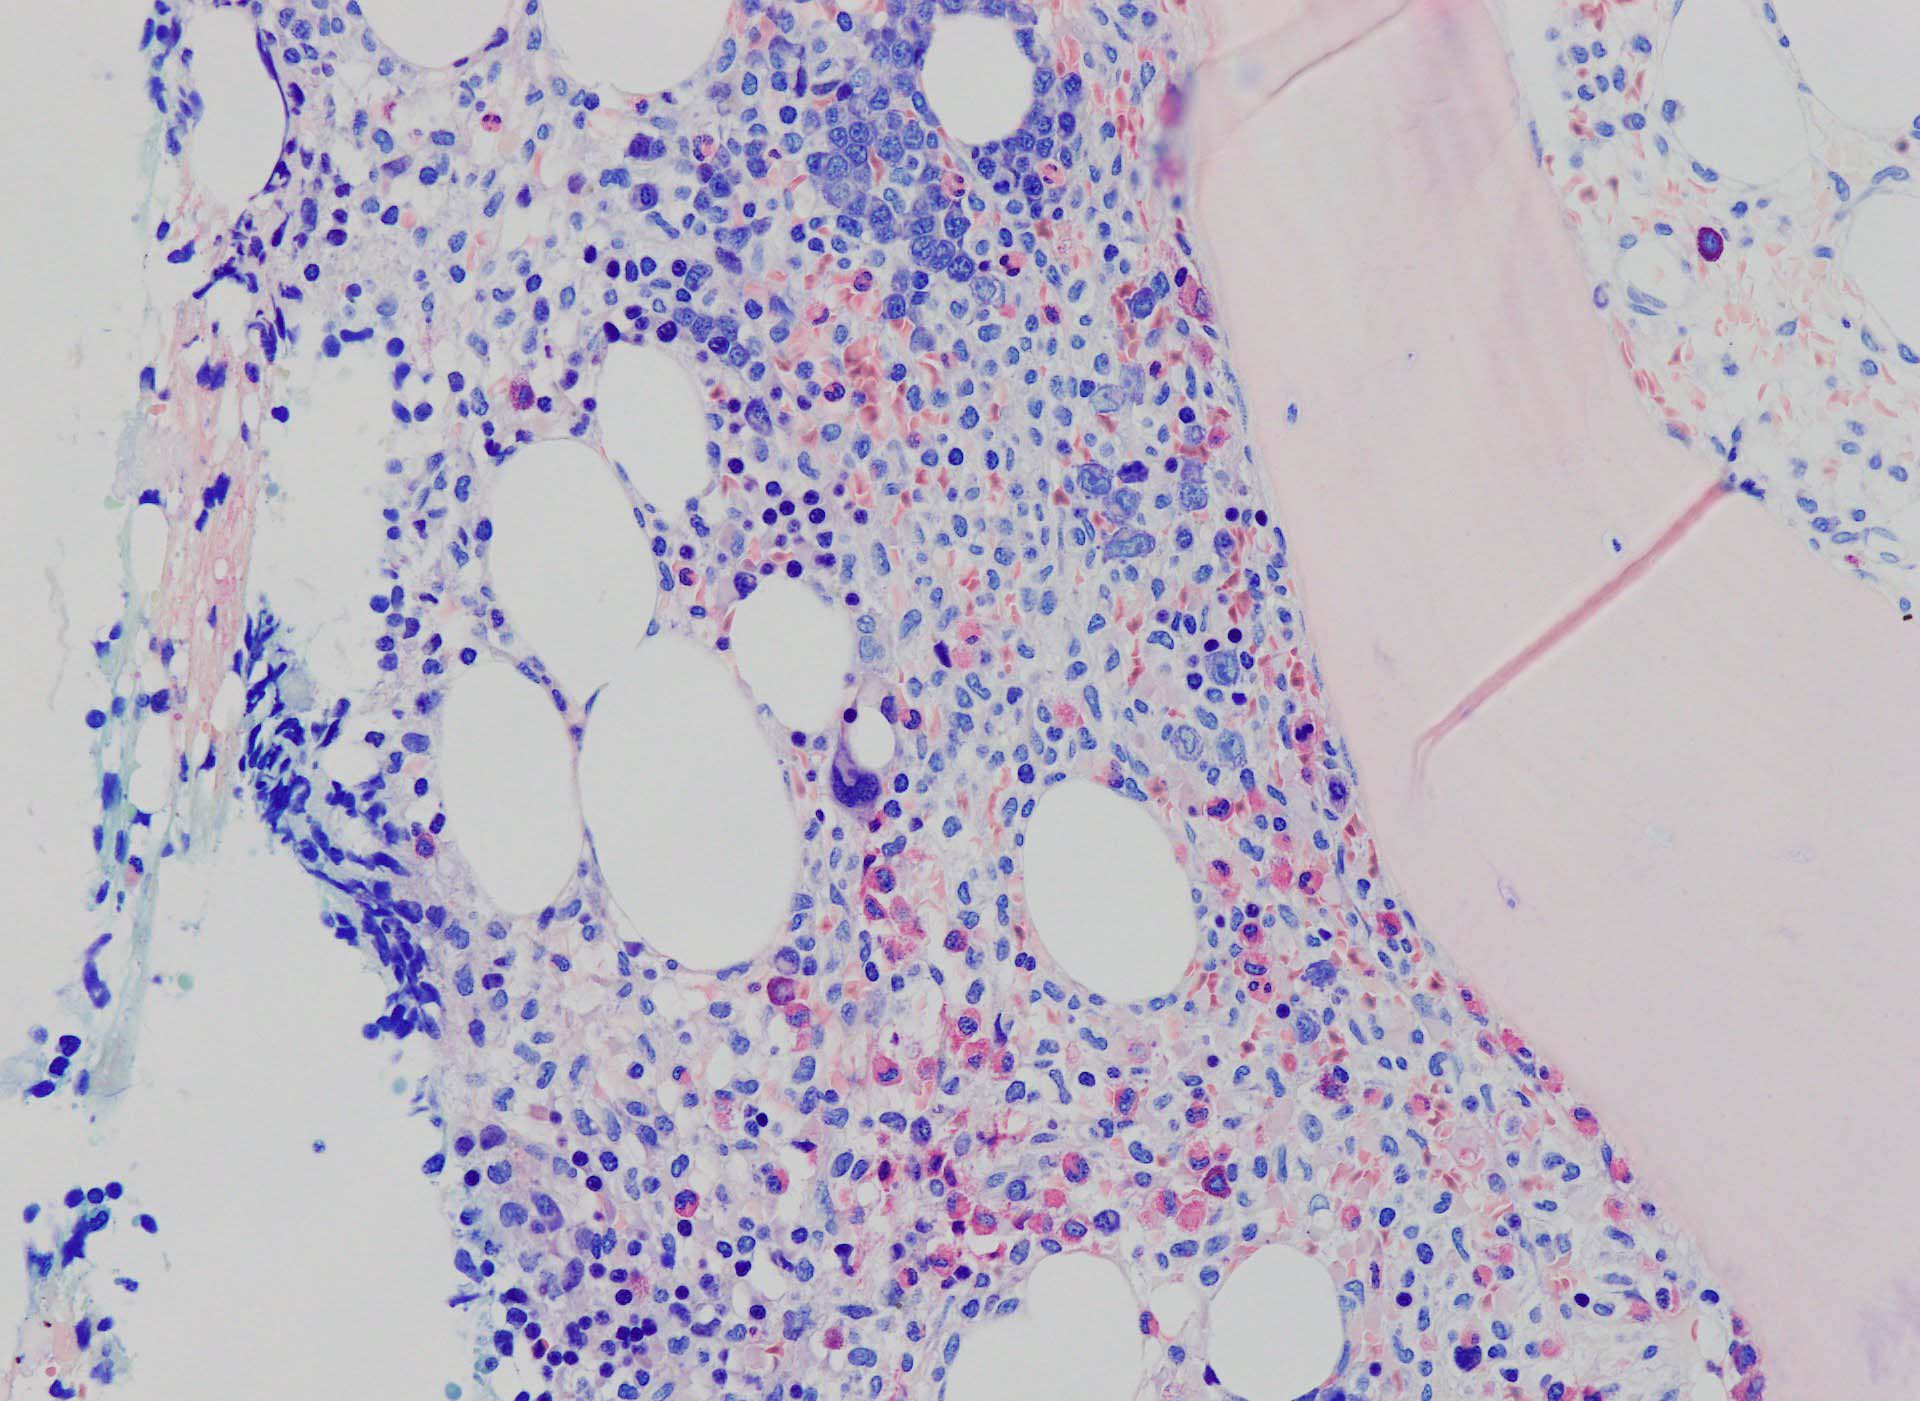

骨髄生検組織を使ったFCMのため, 細胞数が少数であるがCD19, CD20陽性のB-cellが優位で, lambda LC > kappa LCの偏倚がみられclonalな増殖が考えられる. B-cellはCD11c, CD25も発現している. Hairy cell leukaemiaが疑われる. CD103はこのFCMセットには組み込みがなかった.

Hairy-FCM のコピー.jpg ASD-up-PAX5ok.jpg びまん性にPAX5陽性の小型B-cellsが増殖している.

増殖細胞はCD20(相変わらずべったり染まる), CD19, PAX5陽性 CD25陽性.